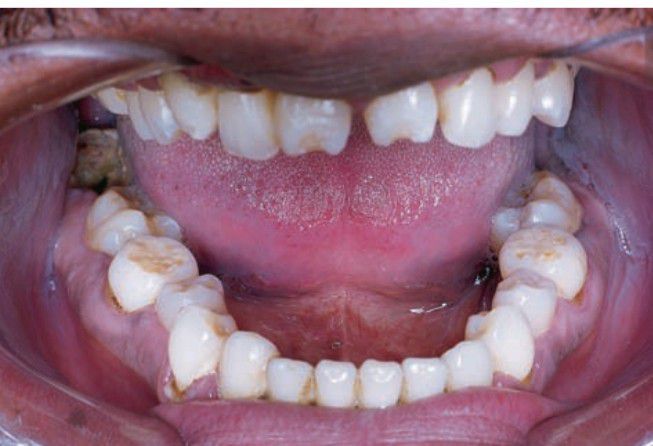

Congenital syphilis

This clinical picture shows mulberry molars and notched incisors as seen in congenital syphilis.